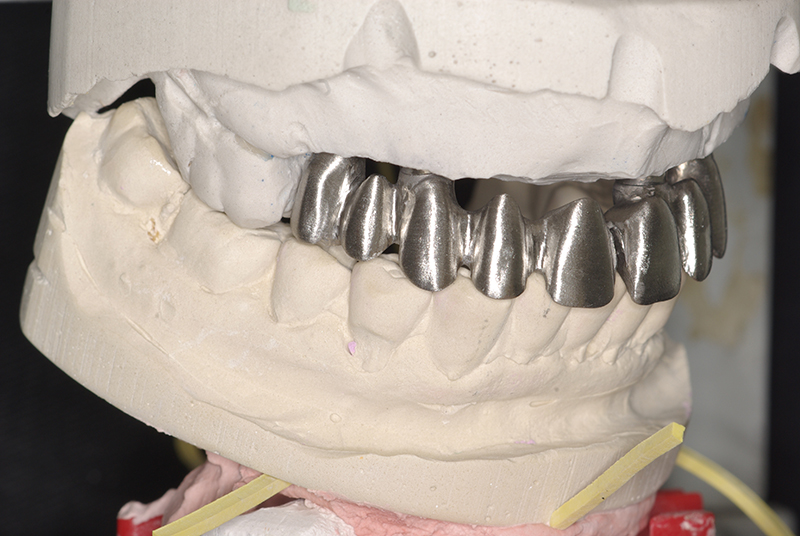

Tecnologia CAD CAM para Maior Precisão e Conforto

Utilizamos a tecnologia CAD CAM, um sistema avançado que possibilita a confecção precisa das próteses dentárias diretamente sobre os implantes. Esse método inovador garante um ajuste perfeito, um resultado estético superior e proporciona muito mais conforto e durabilidade. Com o CAD CAM, nossos pacientes contam com um processo mais rápido e previsível para alcançar o sorriso desejado.